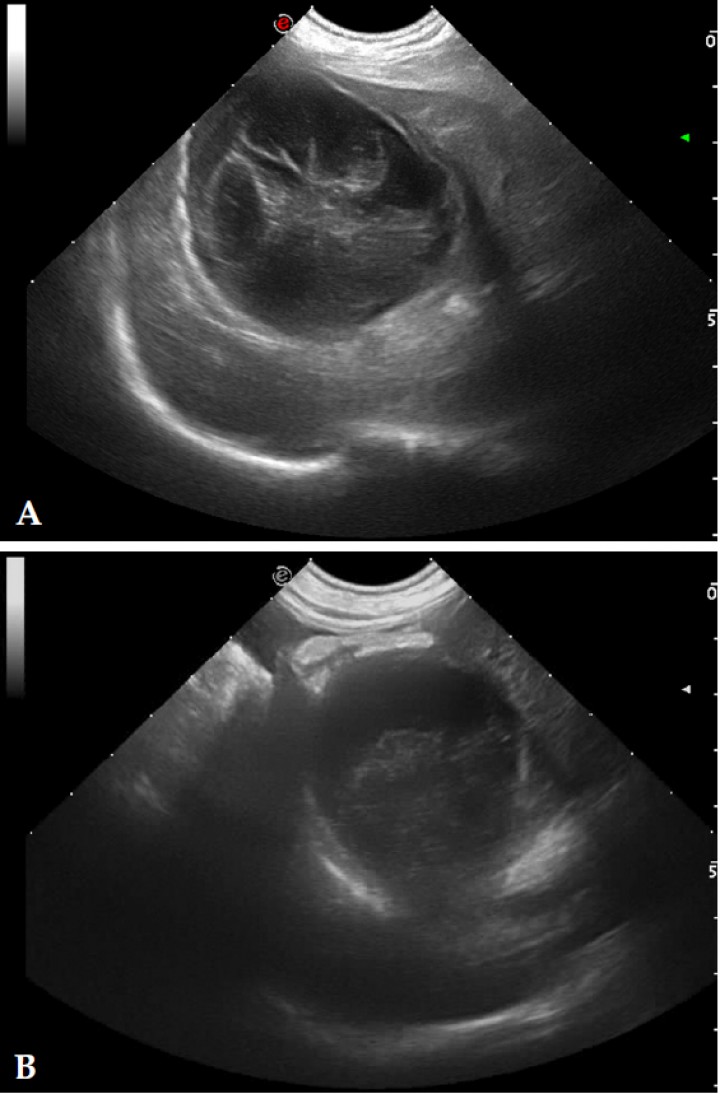

El examen ecográfico fue realizado con sondas semiconvex (3-9 MHz) o lineales (4-13 MHz) (Esaote, Mylab 70, Barcelona, España) según el tamaño del paciente; los animales se posicionaban en decúbito lateral, supino o en estación para confirmar que el contenido de la vesícula biliar era inmóvil. En el examen ecográfico se evaluó el modelo del contenido biliar, grosor de la pared (normal < 3 mm),[ Spaulding KA. Ultrasound corner: Gallbladder Wall thickness. Vet Radiol & Ultrasound 1993; 34:270-272. ] aspecto del tejido adyacente a la vesícula, ecogenicidad del hígado (normal, hiperecogénico, hipoecogénico, o heterogéneo), si existía efusión peritoneal y alteraciones ecográficas en otros órganos. El grado de distensión de la vesícula biliar se evaluó en corte longitudinal (valores de referencia: longitud 3–7,8 cm y profundidad 1,4–4,3 cm) y en corte transversal (valores de referencia: anchura 1,8–4,9 cm y profundidad 1,5–4,1 cm).[ Atalan G, Barr FJ, Holt PE: Estimation of the volumen of the gall bladder of 32 dogs from linear ultrasonographic measurements. Vet Rec, 2007;160: 118-122. [PubMed] ] El modelo del contenido de la vesícula biliar se dividió en 5 tipos (clasificación modificada de JG Besso[ Besso JG, Wrigley RH, Gliatto JM, Webster CRL: Ultrasonographic appearance and clinical fidings in 14 dogs with mucocele. Vet Radiol & Ultrasound, 2000; 41: 261-271. [PubMed] ] y J Choi[ Choi J, Kim A, Keh S, Oh J, Kim H, Yoon J. Comparison between ultrasonographic and clinical fidings in 43 dogs with gallbladder mucoceles. Vet Radiol & Ultrasound, 2014; 55:202-207. [PubMed] ]): Tipo I, sedimento ecogénico inmóvil (Fig. 1); Tipo II, patrón estriado (sedimento ecogénico inmóvil en el que se visualizan estriaciones hipoecogénicas finas y mal definidas desde el interior hacia la pared de la vesícula; Fig. 2); Tipo III, en forma de estrella (material ecogénico en el centro de la luz vesical que emite prolongaciones hipoecogénicas hacia la periferia presentando forma de estrella; Fig. 3); Tipo IV, combinación de patrón de kiwi-estrella (sedimento ecogénico ocupando la zona central de la vesícula biliar en donde se producen prolongaciones con finas estriaciones hacia la periferia; Fig. 4), Tipo V, modelo de kiwi (material ecogénico inmóvil con finas estriaciones hipoecogénicas atravesándolo y ocupando el centro de la luz vesical; Fig. 5).

<p>Imagen ecográfica de la vesícular biliar en corte longitudinal. Modelo de mucocele biliar de Tipo II: se visualiza contenido en la vesícula biliar ecogénico inmóvil adherido a la pared y una moderada cantidad de sedimento móvil.</p>

Figura 2

Imagen ecográfica de la vesícular biliar en corte longitudinal. Modelo de mucocele biliar de Tipo II: se visualiza contenido en la vesícula biliar ecogénico inmóvil adherido a la pared y una moderada cantidad de sedimento móvil.

<p>Imagen ecográfica de la vesícula biliar en corte longitudinal. Modelo de mucocele biliar de Tipo IV: en el interior de la vesícula biliar se aprecian dos tipos de sedimentos inmóviles; uno ocupando la zona central con estriaciones hacia la periferia y otro de aspecto más amorfo sin estriaciones hacia la periferia.</p>

Figura 4

Imagen ecográfica de la vesícula biliar en corte longitudinal. Modelo de mucocele biliar de Tipo IV: en el interior de la vesícula biliar se aprecian dos tipos de sedimentos inmóviles; uno ocupando la zona central con estriaciones hacia la periferia y otro de aspecto más amorfo sin estriaciones hacia la periferia.